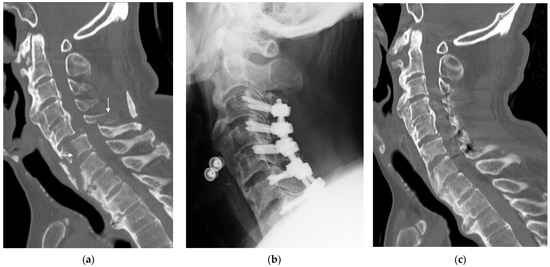

Figure 2.

A representative case of cervical spinal cord injury with diffuse idiopathic skeletal hyperostosis. A 57-year-old man presented with a C5–6 three-column fracture after low-impact trauma. The preoperative AIS grade was B. We performed C3–7 posterior decompression and fusion surgery 6 h after the injury. Bone union was confirmed 3 months after surgery. One year after surgery, the patient recovered to AIS grade D. (a) Preoperative midsagittal computed tomography (CT) image with white arrows indicating the fracture line. (b) Radiograph 3 months after surgery. (c) Postoperative midsagittal CT 3 months after surgery (bone union confirmed).